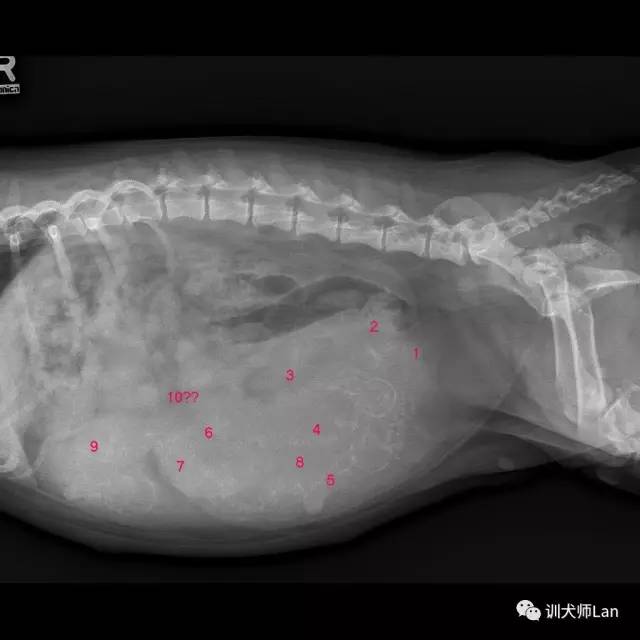

在预产期前两周通过照X光可以准确估计幼犬出生的大小。

X光可以在怀孕45天后,看到幼犬的骨骼轮廓。